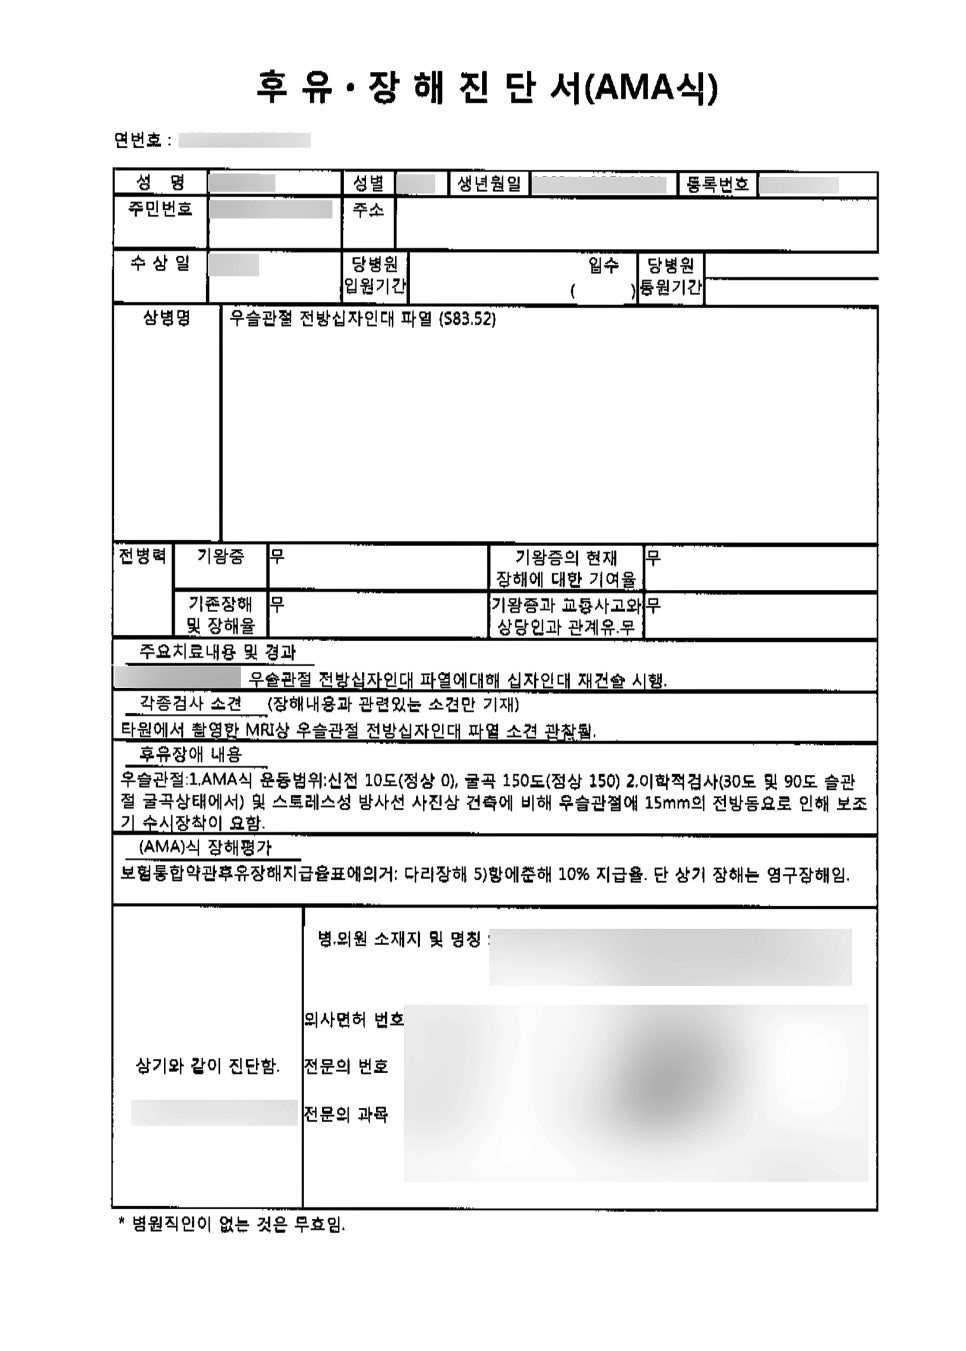

어떻게 믿을 수 있어? 라고 생각하셔도~ 오늘 보시는 진단서나 후유장해진단서를 함께 보시고 나면 생각이 바뀌실 겁니다 ^_^

친구들과 가진 좋은 시간에.. 십자인대파열로 후유장해까지 겪게 되셨으니 정말 마음이 안좋으실거예요 ㅠㅠ 진단명은, 진단서에서 나와있는 것처럼

[우측 슬관절 전방십자인대파열]

관절경을 이용하여 전방십자인대 제건술을 시행하였으며, 수술일로 부터 미발견증 및 합병증 이 없는한 6주간의 가료가 필요한 것으로 사료 되었다고 나와있는 것을 확인할 수 있습니다. 진단서에 나와있는 진단명을 문의시 정확하게 알려주시면 빠른 상담에 많은 도움이 됩니다^^

개인보험을 통해서만 1,050만원을 받으셨어요~ 보상금을 얼마나 받을 수 있는 것인지 제일 궁금 하실텐데요, 이런 후유장해시 수술일/사고일로 부터 6개월은 지나야 후유장해진단이 가능해져요!